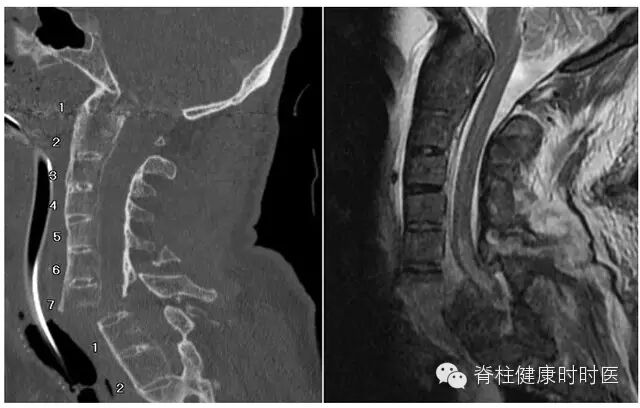

100例患者(205处骨折)MRI检查提示骨髓水肿。对骨折进行分类后再分析,骨折类型与骨髓水肿密切相关,92例患者的188处压缩骨折,与骨髓水肿及程度相关。齿状突骨折 42 例,基本没有骨髓水肿(图 1)。12 例经椎间和 / 或邻近终板的骨折,亦无骨髓水肿(图 2)。10 例强直性脊柱炎患者,经椎间 - 终板或椎体的骨折,骨髓水肿有限或没有(图 3)。6 例 Chance 骨折,均无骨髓水肿(图 4)。

图 2 通过椎间盘和 / 或软骨终板的骨折。左图:CT 示 C5-6 椎间隙轻度增宽。右图:短时间反转恢复序列 MRI 示椎间隙 T2 相高信号,但椎体中没有。

图 3 强直性脊柱炎情况下的新鲜过伸型骨折。左图:经 C7 椎体终板的骨折,颈椎向前移位。右图:椎体无骨髓水肿。可见脊髓压迫和血肿,椎前大量血肿,棘突间异常信号示损伤。